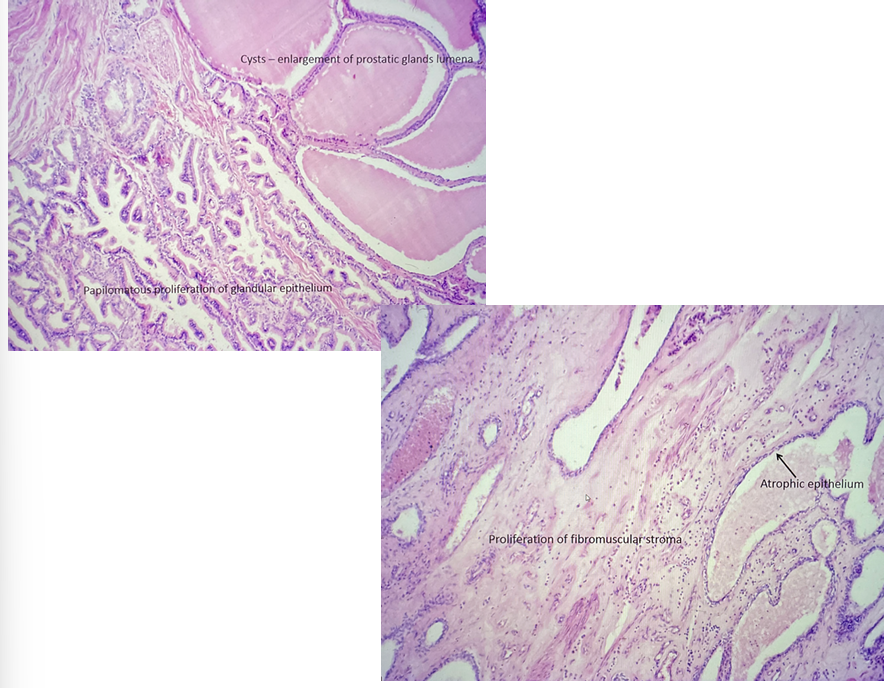

hypertrophy of prostata

this is?